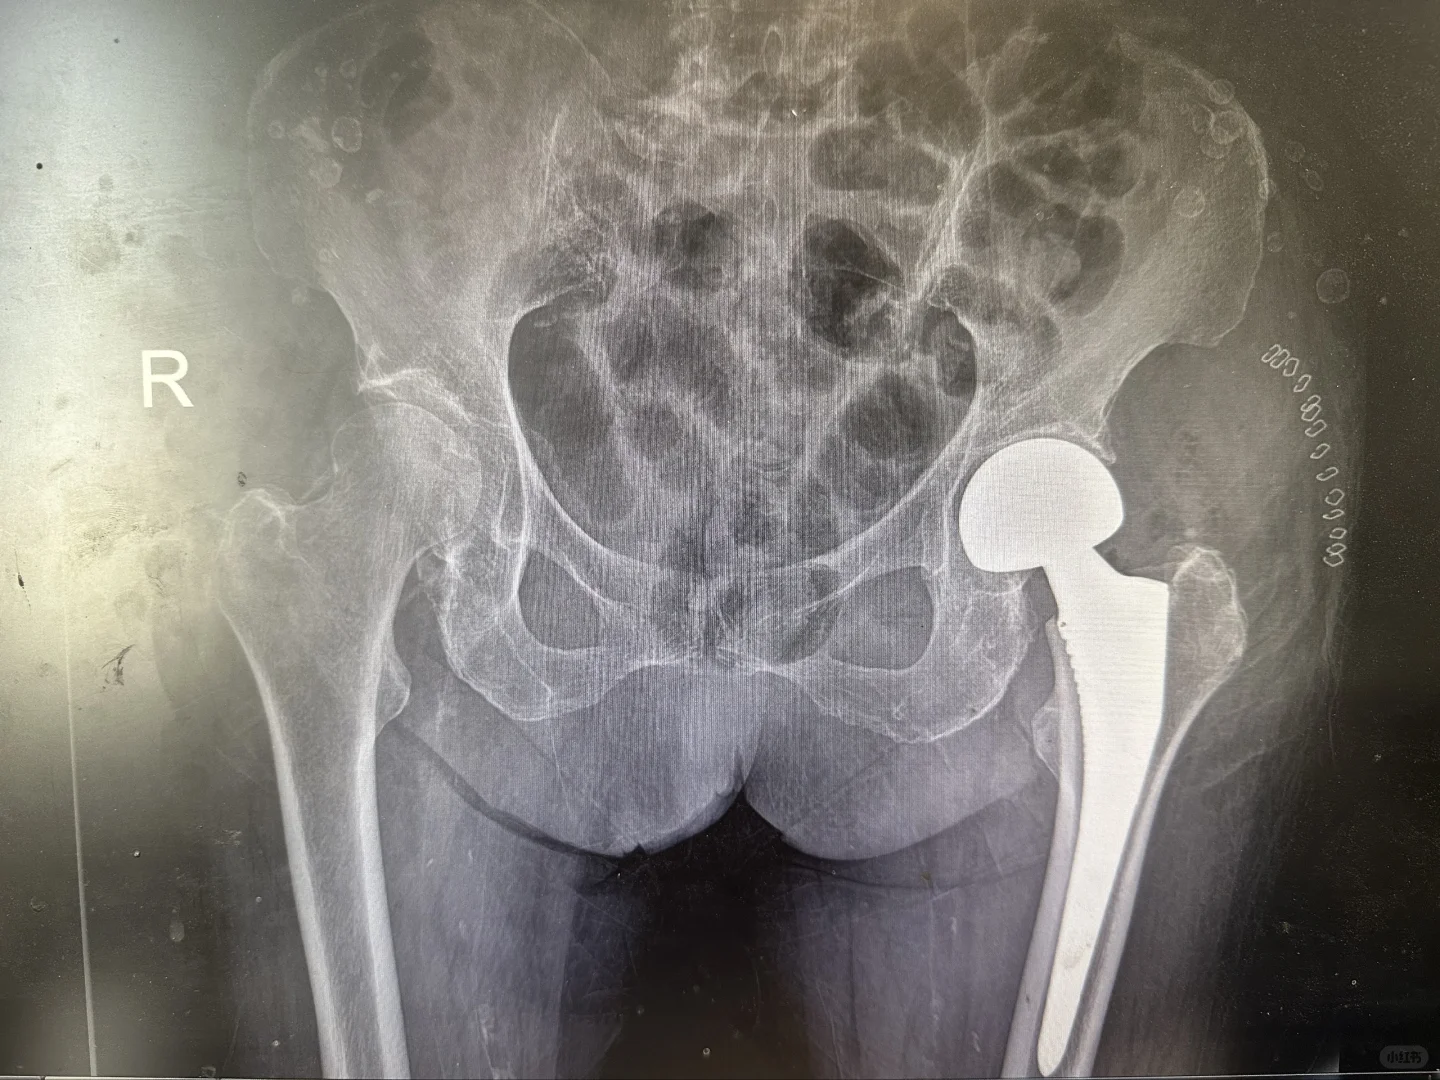

关节置换

髋膝关节置换手术是二十世纪以来最成熟的手术,1小时的手术时间能够给患者带来关节的重生,从此告别让人无法忍受的疼痛,回归正常生活,老人上下楼梯爬山跳舞不是梦。

给大家看看我们的手术器械和术后影像,抡大锤的马医生在线回复您的疑问,点个关注,持续解答。